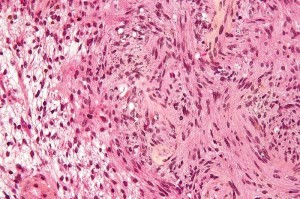

El nuevo estudio mostró que el medicamento candidato-conocido como FRAX97-ralentiza la proliferación y la progresión de las células tumorales en modelos animales de la neurofibromatosis de tipo 2. Este tipo heredado de cáncer, causado por mutaciones en el gen NF2 anti-tumoral, conduce a los tumores del nervio auditivo que conecta el oído interno hasta el cerebro.

El nuevo compuesto, desarrollado originalmente para el tratamiento de enfermedades neurodegenerativas, se dirige a una familia de proteínas conocidas como quinasas activadas por p21 o Paks. Estas quinasas (enzimas que añaden un grupo fosfato a otras proteínas y cambian su función) desempeñan un papel crítico en el desarrollo de la neurofibromatosis de tipo 2. PAK1 también ha sido implicado en el crecimiento de los cánceres de mama y de pulmón.